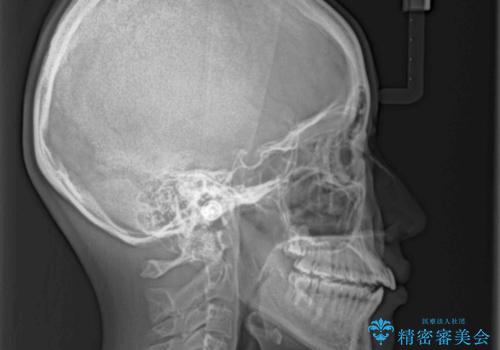

オープンバイトのインビザラインを用いた再矯正

- 矯正治療の後戻りを気にして来院された患者様です。

オープンバイト(前歯の開咬)と下顎骨の偏位による不正咬合が認められました。

骨格の偏位による不正咬合は改善しきれないことを理解いただいた上で、インビザラインにて矯正治療を行うこととしました。

オープンバイトは後戻りを起こしやすいため、極力そのリスクを軽減するため、奥歯を圧下させるように治療を進めていきました。

下顎骨の偏位が顕著であったため、上下の正中を合わせることはできませんでしたが、患者様には大変満足していただきました。